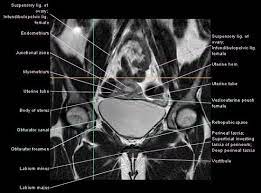

Pelvis Cross Sectional Mri Imagelarge Jpg 550 406 Diagnostic Imaging Mri Radiology Imaging

Magnetic resonance imaging or mri of the female pelvis offers a unique display of the pelvic anatomy, including a woman's ovaries, uterus, and fallopian tubes. Start studying normal female pelvis anatomy. With its help, it is realistic to study the female pelvis and get comprehensive information about the state of all organs of the human body.